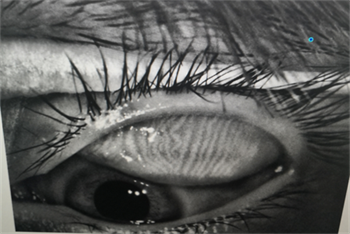

06、螨蟲(chóng)檢查

每一個(gè)眼瞼拔3根睫毛,檢查有沒(méi)有蠕形螨,以及數(shù)量多少。

如果任意一個(gè)眼瞼螨蟲(chóng)數(shù)量不少于3只,就需要除螨治療了。眼瞼螨蟲(chóng)過(guò)多會(huì)造成機(jī)械性損傷,附帶細(xì)菌還會(huì)引起瞼緣感染,后續(xù)會(huì)有干癢、紅腫、分泌物增多、睫毛脫落等一系列問(wèn)題。